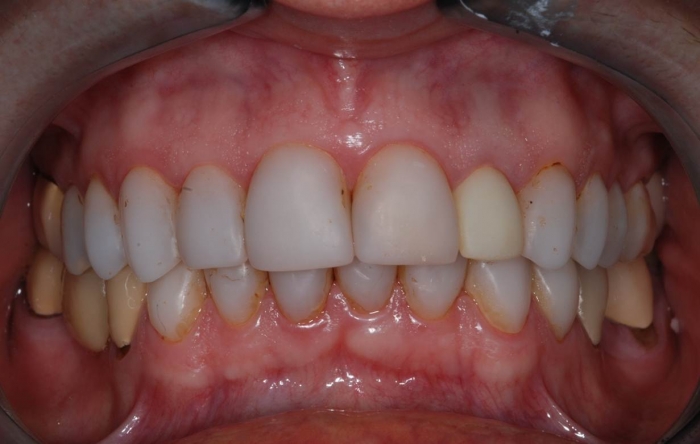

Imagens com facetas e prótese fixa em porcelana sobre implante

Sorriso final